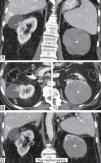

Se presenta como un tumor periférico circunscrito (pequeño y homogéneamente sólido o mayor quístico-hemorrágico) o como una lesión infiltrante e invasora de venas, con peor pronóstico.

Por su baja densidad vascular, el realce es menor que en otras neoplasias renales, lo que facilita su caracterización. En tomografía computarizada puede no realzar de manera concluyente, y entonces es indistinguible de un quiste hiperatenuante. La ecografía con contraste y la resonancia magnética son más sensibles para detectar vascularización. Son además característicos un patrón vascular específico, hipointensidad en T2, restricción de la difusión del agua y aumento de señal en fase opuesta.

It presents as a circumscribed peripheral tumor (small and homogeneously solid or larger and cystic/hemorrhagic) or as an infiltrating lesion that invades the veins, which has a worse prognosis.

Due to their low vascular density, papillary renal cell carcinomas enhance less than other renal tumors, and this facilitates their characterization. On computed tomography, they might not enhance conclusively, and in these cases they are impossible to distinguish from hyperattenuating cysts. Contrast-enhanced ultrasonography and magnetic resonance imaging are more sensitive for detecting vascularization. Other characteristics include a specific vascular pattern, hypointensity on T2-weighted images, restricted water diffusion, and increased signal intensity in opposed phase images.